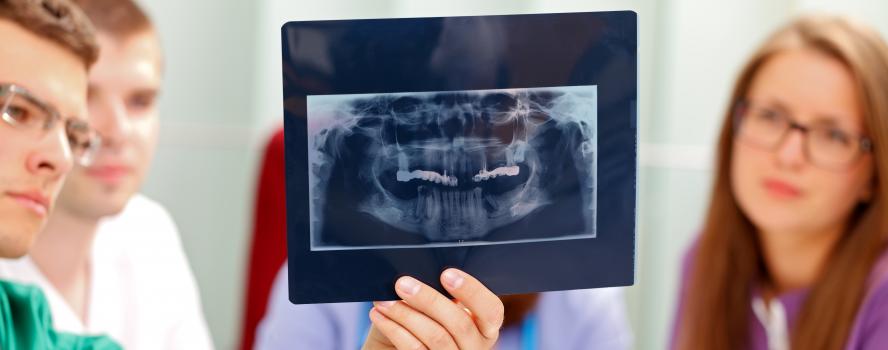

We provide emergency dental treatment for existing patients. Our goal is to see you on the same day as your emergency. Call our office if you’ve suffered an injury, broken a tooth, filling or crown, or are suffering from a severe toothache.